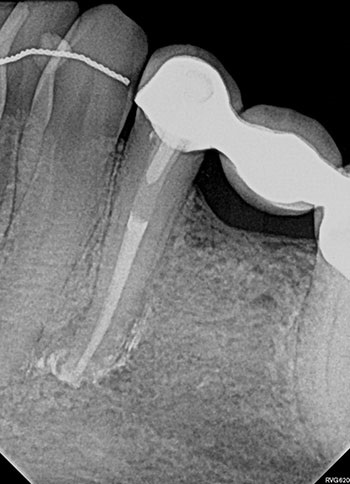

Case 5: Bilateral lesions

This patient was very worried that she was going to lose her front tooth, #8. Her dentist was concerned that the root had been split by a large, tapered post given the context of the bilateral radiolucencies located at the bottom of the post.

No crack was seen when the post was removed, nor were any lateral canals located. This tooth was treated in three visits over six months using a calcium hydroxide intracanal medicament. It is possible that a nidus of bacteria remained in the gap between the obturation and the post.

The patient’s symptoms resolved after the first visit. The case was obturated after confirming full bony healing. She is still extremely appreciative of the efforts made to save her front tooth.

Fig. 19: Preop PA.